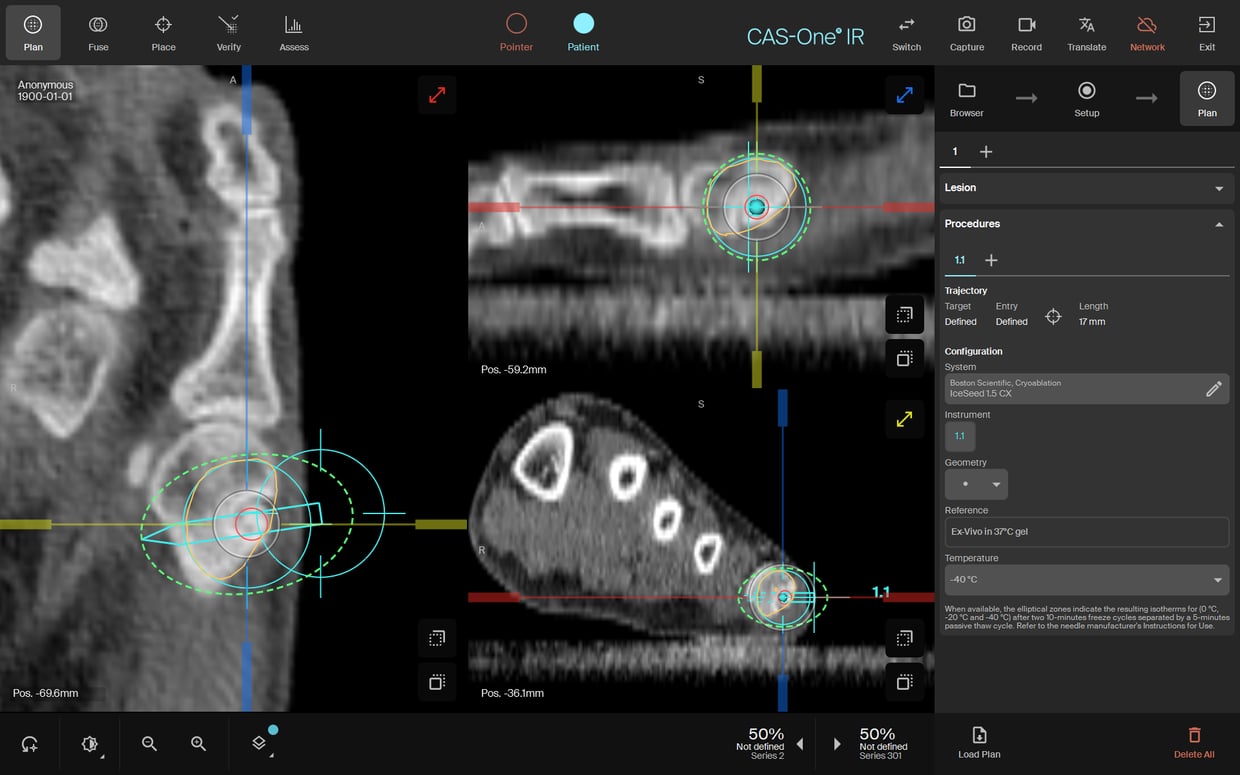

Planning of the trajectory and estimated cryoabaltion zone

Alignment of the aiming device (done as a three slice fluoro to reduce radiation)

IceSeed cryoprobe (Boston Scientific) introduced through the biopsy needle

Cryoablation performed for 10 minutes at 60% energy